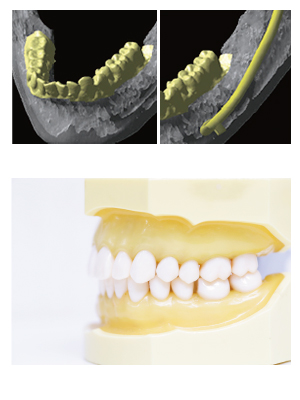

歯科技工士との連携

咬合まで考慮した治療